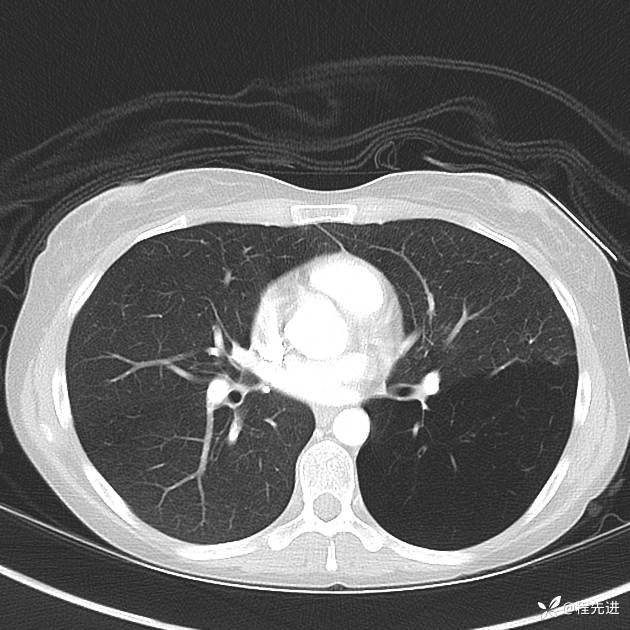

患者性别:女

患者年龄:25岁

简要病史:下胸部疼痛3天

CT增强: